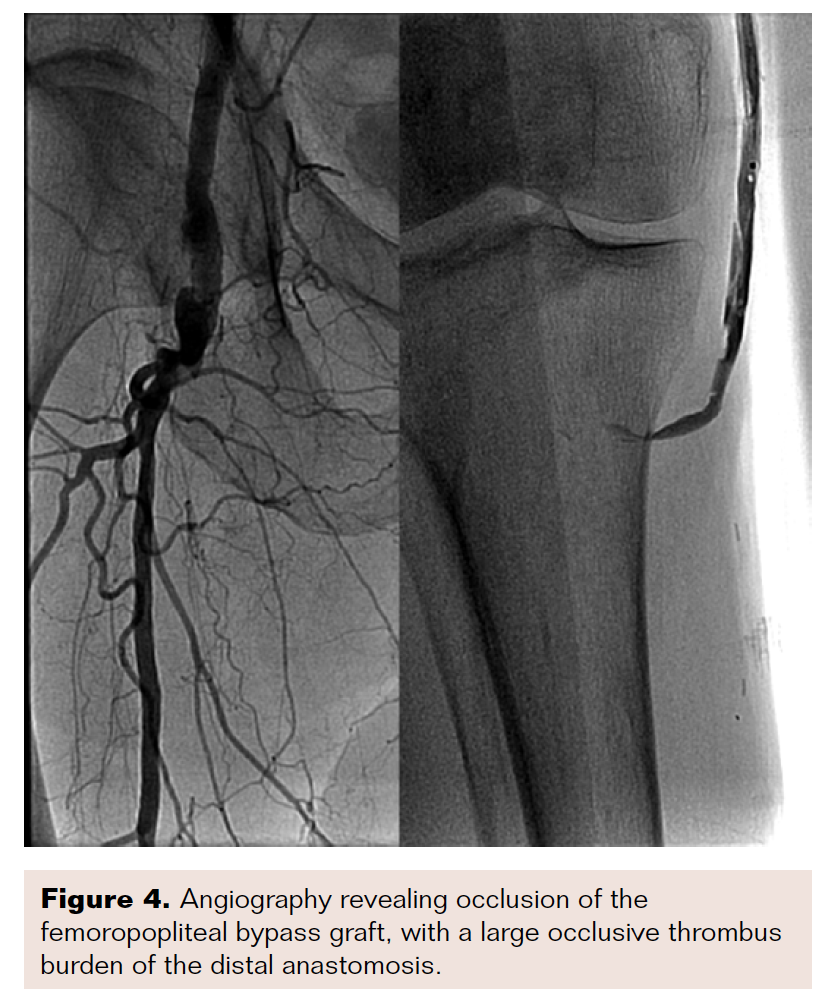

A 70-year-old man with a history of left above-knee amputation and recent right femoropopliteal bypass presented to the emergency department with Rutherford class IIb symptoms. Computed tomography angiography demonstrated occlusion of the bypass graft with poor distal flow.

Angiography showed complete occlusion of the graft and very poor run-off past the distal anastomotic site (Figure 4). With some difficulty, a wire and support catheter were passed down into the native tibioperoneal trunk. Angioplasty was performed at the proximal and distal anastomotic sites to increase inflow and outflow. After multiple inflations, a 30 cm Ekos catheter was placed and acoustic pulse thrombolysis was initiated.